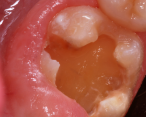

A 7-year-old presented with a malformed, sensitive molar.

Figure 14

A 7-year-old boy had a newly erupted mandibular right permanent first molar. The tooth had hypoplastic and hypocalcification malformation and associated dental caries (Figure 14). After inferior alveolar block anesthetic injection, the rubber dam was applied using the slit-dam method.8 Occlusal-distobuccal preparation was completed using a water-cooled, coarse-grit cylindrical diamond bur. All carious and chalky hypocalcified tooth structure was removed. Preparation design included mechanical undercut retention form (Figure 15).  After placement of an orthodontic band as a matrix, without removal of the rubber dam clamp, 5% glutaraldehyde/HEMA desensitizing solution was applied and agitated with a microbrush for two 60-second exposures, and air-dried after each application (Figure 16). A self-etching bonding agent was then painted over the enamel and dentin and spread to a thin layer with the air syringe. After 10 seconds of light exposure, an RMGI bioactive ionic resin-based composite was injected to overfill, in one portion. The restoration was trimmed with slow-speed diamond burs, and the self-etching bonding agent was applied over the composite surfaces and surrounding enamel. The light beam was applied for another 10 seconds (Figure 17).  Occlusion was determined using articulating paper, and corrections were made (Figure 18). The occlusal view of the restored molar is shown 20 months after treatment (Figure 19).